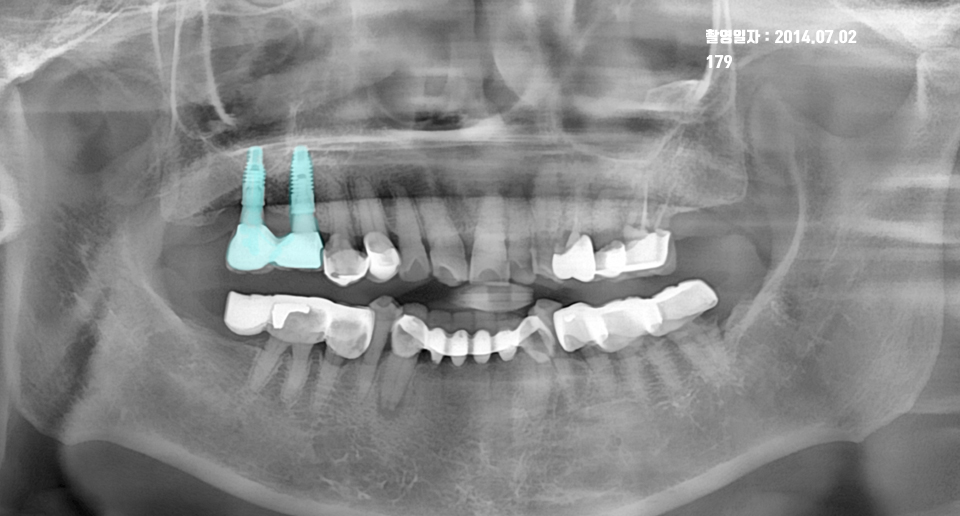

1. 2014년: 임플란트 보철 직후 (초기 안정기)

첫 번째 사진은 2014년 7월, 상악(위) 우측 어금니 임플란트 보철이 성공적으로 올라간 모습입니다.

- 상태: 임플란트 나사선(픽스처) 주변으로 치조골이 빈틈없이 밀도 있게 감싸고 있는 것을 확인할 수 있습니다.

- 특이사항: 수술 직후의 치조골 높이가 매우 안정적이며, 보철물과 잇몸 라인이 조화롭게 형성된 시기입니다.